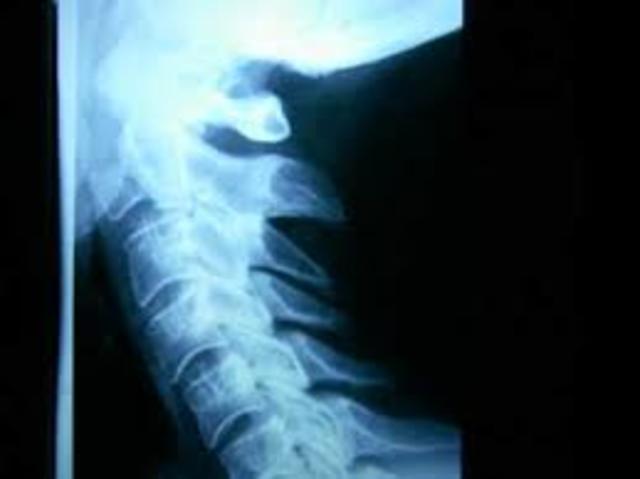

8 meses después de que inicie mi trabajo en Liverpool, un accidente laboral cambió mi vida, pues al caer en mi cabeza una garrocha de trabajo me limito durante 4 meses, dejando secuelas en mis cervicales desplazamiento de la 4 y 5 vértebra, impidiendo con ello realizar mi trabajo.

En este año por situaciones de salud abandone la unidad de atencion a la violencia, pues mi cuello presentó una crisis que me incapacito de nuevo para trabajar, pues a raíz del accidente una subluxación en la primera vértebra me ocasiona dolor y contracturas en la parte izquierda . y inicie mi propio negocio en alta costura haciendo vestidos de novia y 15 años principalmente